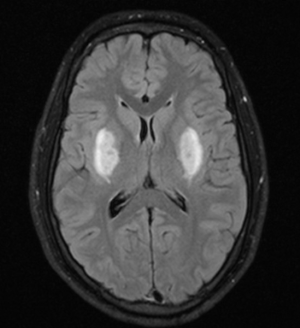

• Exames de imagem (Ressonância e tomografia de crânio): Não são feitos de rotina, mas caso sejam feitos para avaliação do rebaixamento do nível de consciência é possível identificar uma hiperintensidade do putâmen por necrose hemorrágica, além de acometimento do quiasma óptico.

Fonte: Radiopaedia